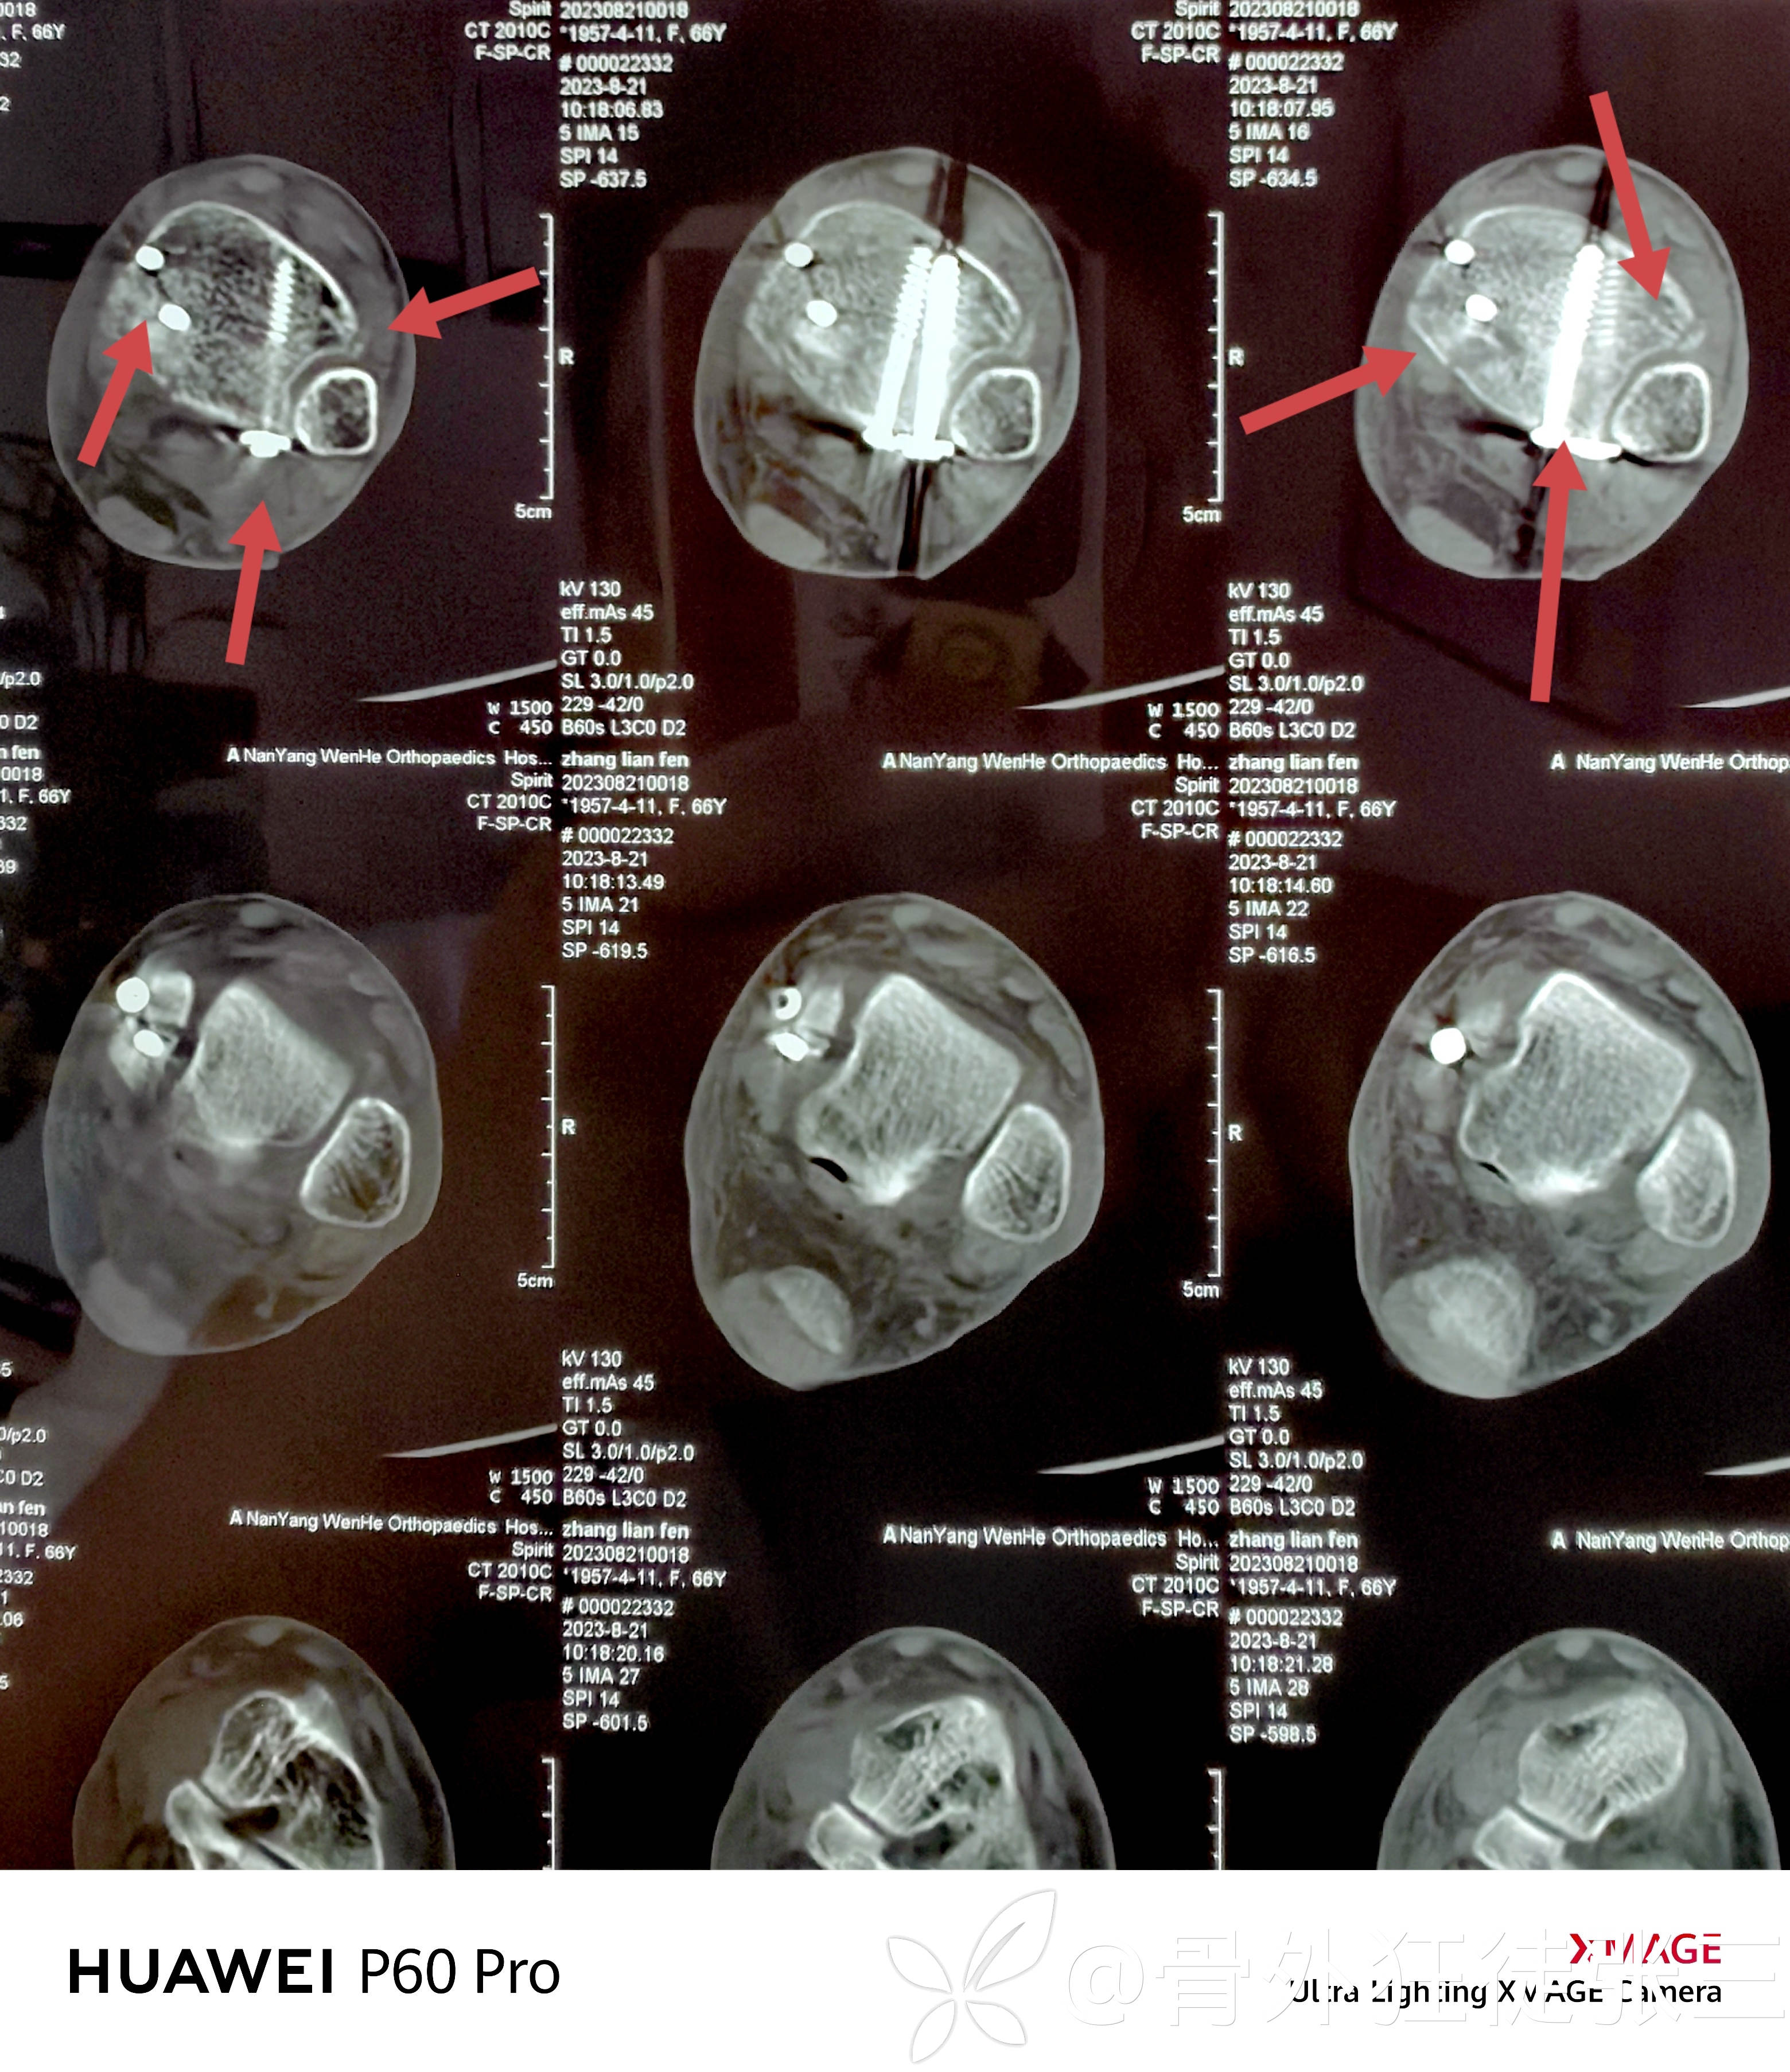

术后CT验证

后踝骨折复位良好

下胫腓位置良好

内踝骨折位置良好。

内踝经皮空心钉小切口不明显